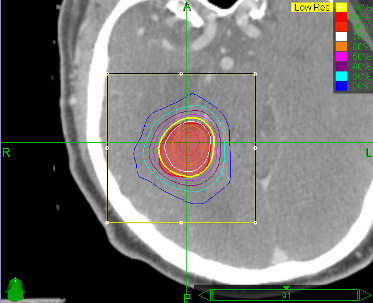

The researchers wanted to find the feasibility of stereotactic radiosurgery (SRS) because it “is an appealing treatment option after previous radiotherapy because of its precision, conformality, and reduced treatment duration.”

From 2002 to 2008, 65 patients received SRS to the oropharynx (13), hypopharynx (8), nasopharynx (7), paranasal sinus (7), neck (7), and other sites (23). Thirty-eight patients were treated definitively and 27 patients with metastatic disease and/or untreated local disease were treated palliatively. Nine patients underwent complete macroscopic resection before SRS. Thirty-three patients received concurrent chemoradiation. The median initial radiation dose was 67 Gy, and the median reirradiation SRS dose was 30 Gy (21–35 Gy) in 2–5 fractions.

Follow-up was on average 16 months for surviving patients. Fifty-six patients were evaluable for response: 30 (54 percent) had complete, 15 (27 percent) had partial, and 11 (20 percent) had no response. The overall survival (OS) for all patients averaged 12 months. For definitively treated patients, the 2-year OS and locoregional control (LRC) rates were 41 percent and 30 percent, respectively. Multivariate analysis demonstrated that higher total dose, surgical resection, and nasopharynx site were significantly associated with improved LRC; surgical resection and nonsquamous histology were associated with improved OS. Seven patients (11 percent) experienced severe reirradiation-related toxicity, including one treatment-attributed death.